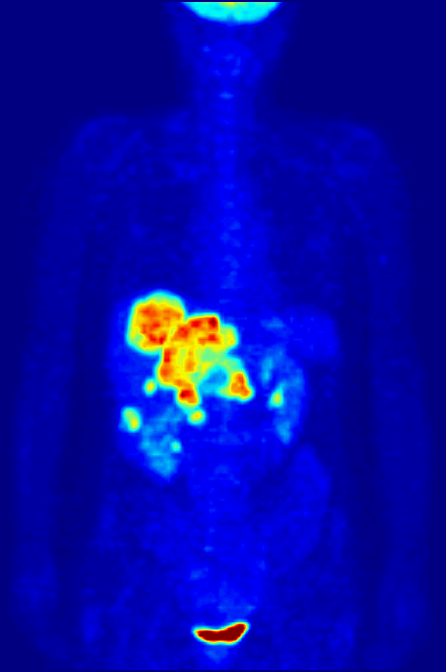

PET全身扫描最大密度投影(MIP)旋转动画:展示经过衰减校正和重建后的PET图像三维效果

- PET扫描图像示例:Wikimedia Commons - PET-image,Public Domain

- PET全身扫描MIP动画:Wikimedia Commons - PET-MIPS-anim,Public Domain